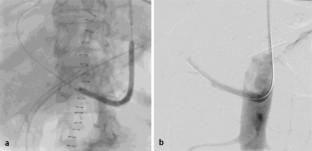

Abb. 1

Abb. 2

Abb. 3

Abb. 4

Abb. 5

Abb. 6